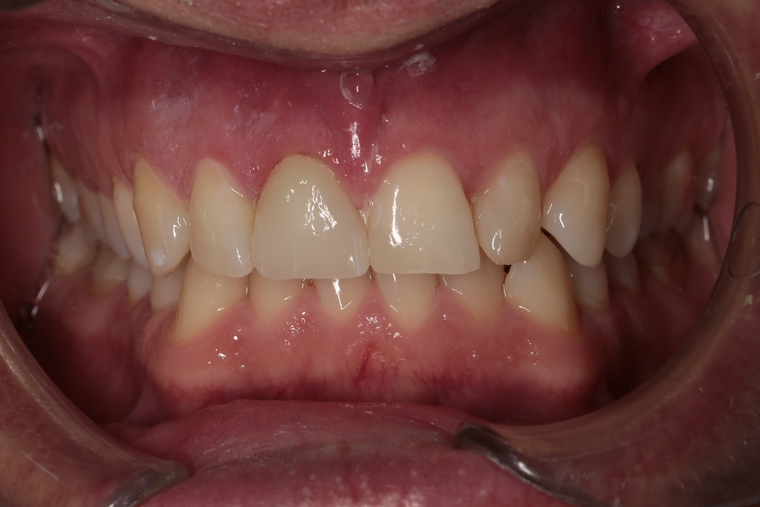

Ein Tätigkeitsschwerpunkt unserer Praxis in Salzburg ist die Implantologie. Wenn ein Zahn fehlt oder entfernt werden muss, sollte immer die Möglichkeit der Implantation im Vordergrund stehen. Ein Implantat verhält sich von den Eigenschaften genau so wie ein natürlicher Zahn. Egal ob nur ein einzelner Zahn vom Zahnarzt ersetzt werden muss oder ein ganzer Kiefer mit festsitzendem Zahnersatz versorgt werden soll, wir finden für Sie eine Möglichkeit, auch wenn die Voraussetzungen ausweglos erscheinen. Wenn möglich versorgen wir unsere Patienten mit Keramikimplantaten. Diese sind immun-neutral und können sehr oft direkt bei der Zahnextraktion eingesetzt werden. Für unsere Patienten ist daher meist nur ein operativer Eingriff notwendig!